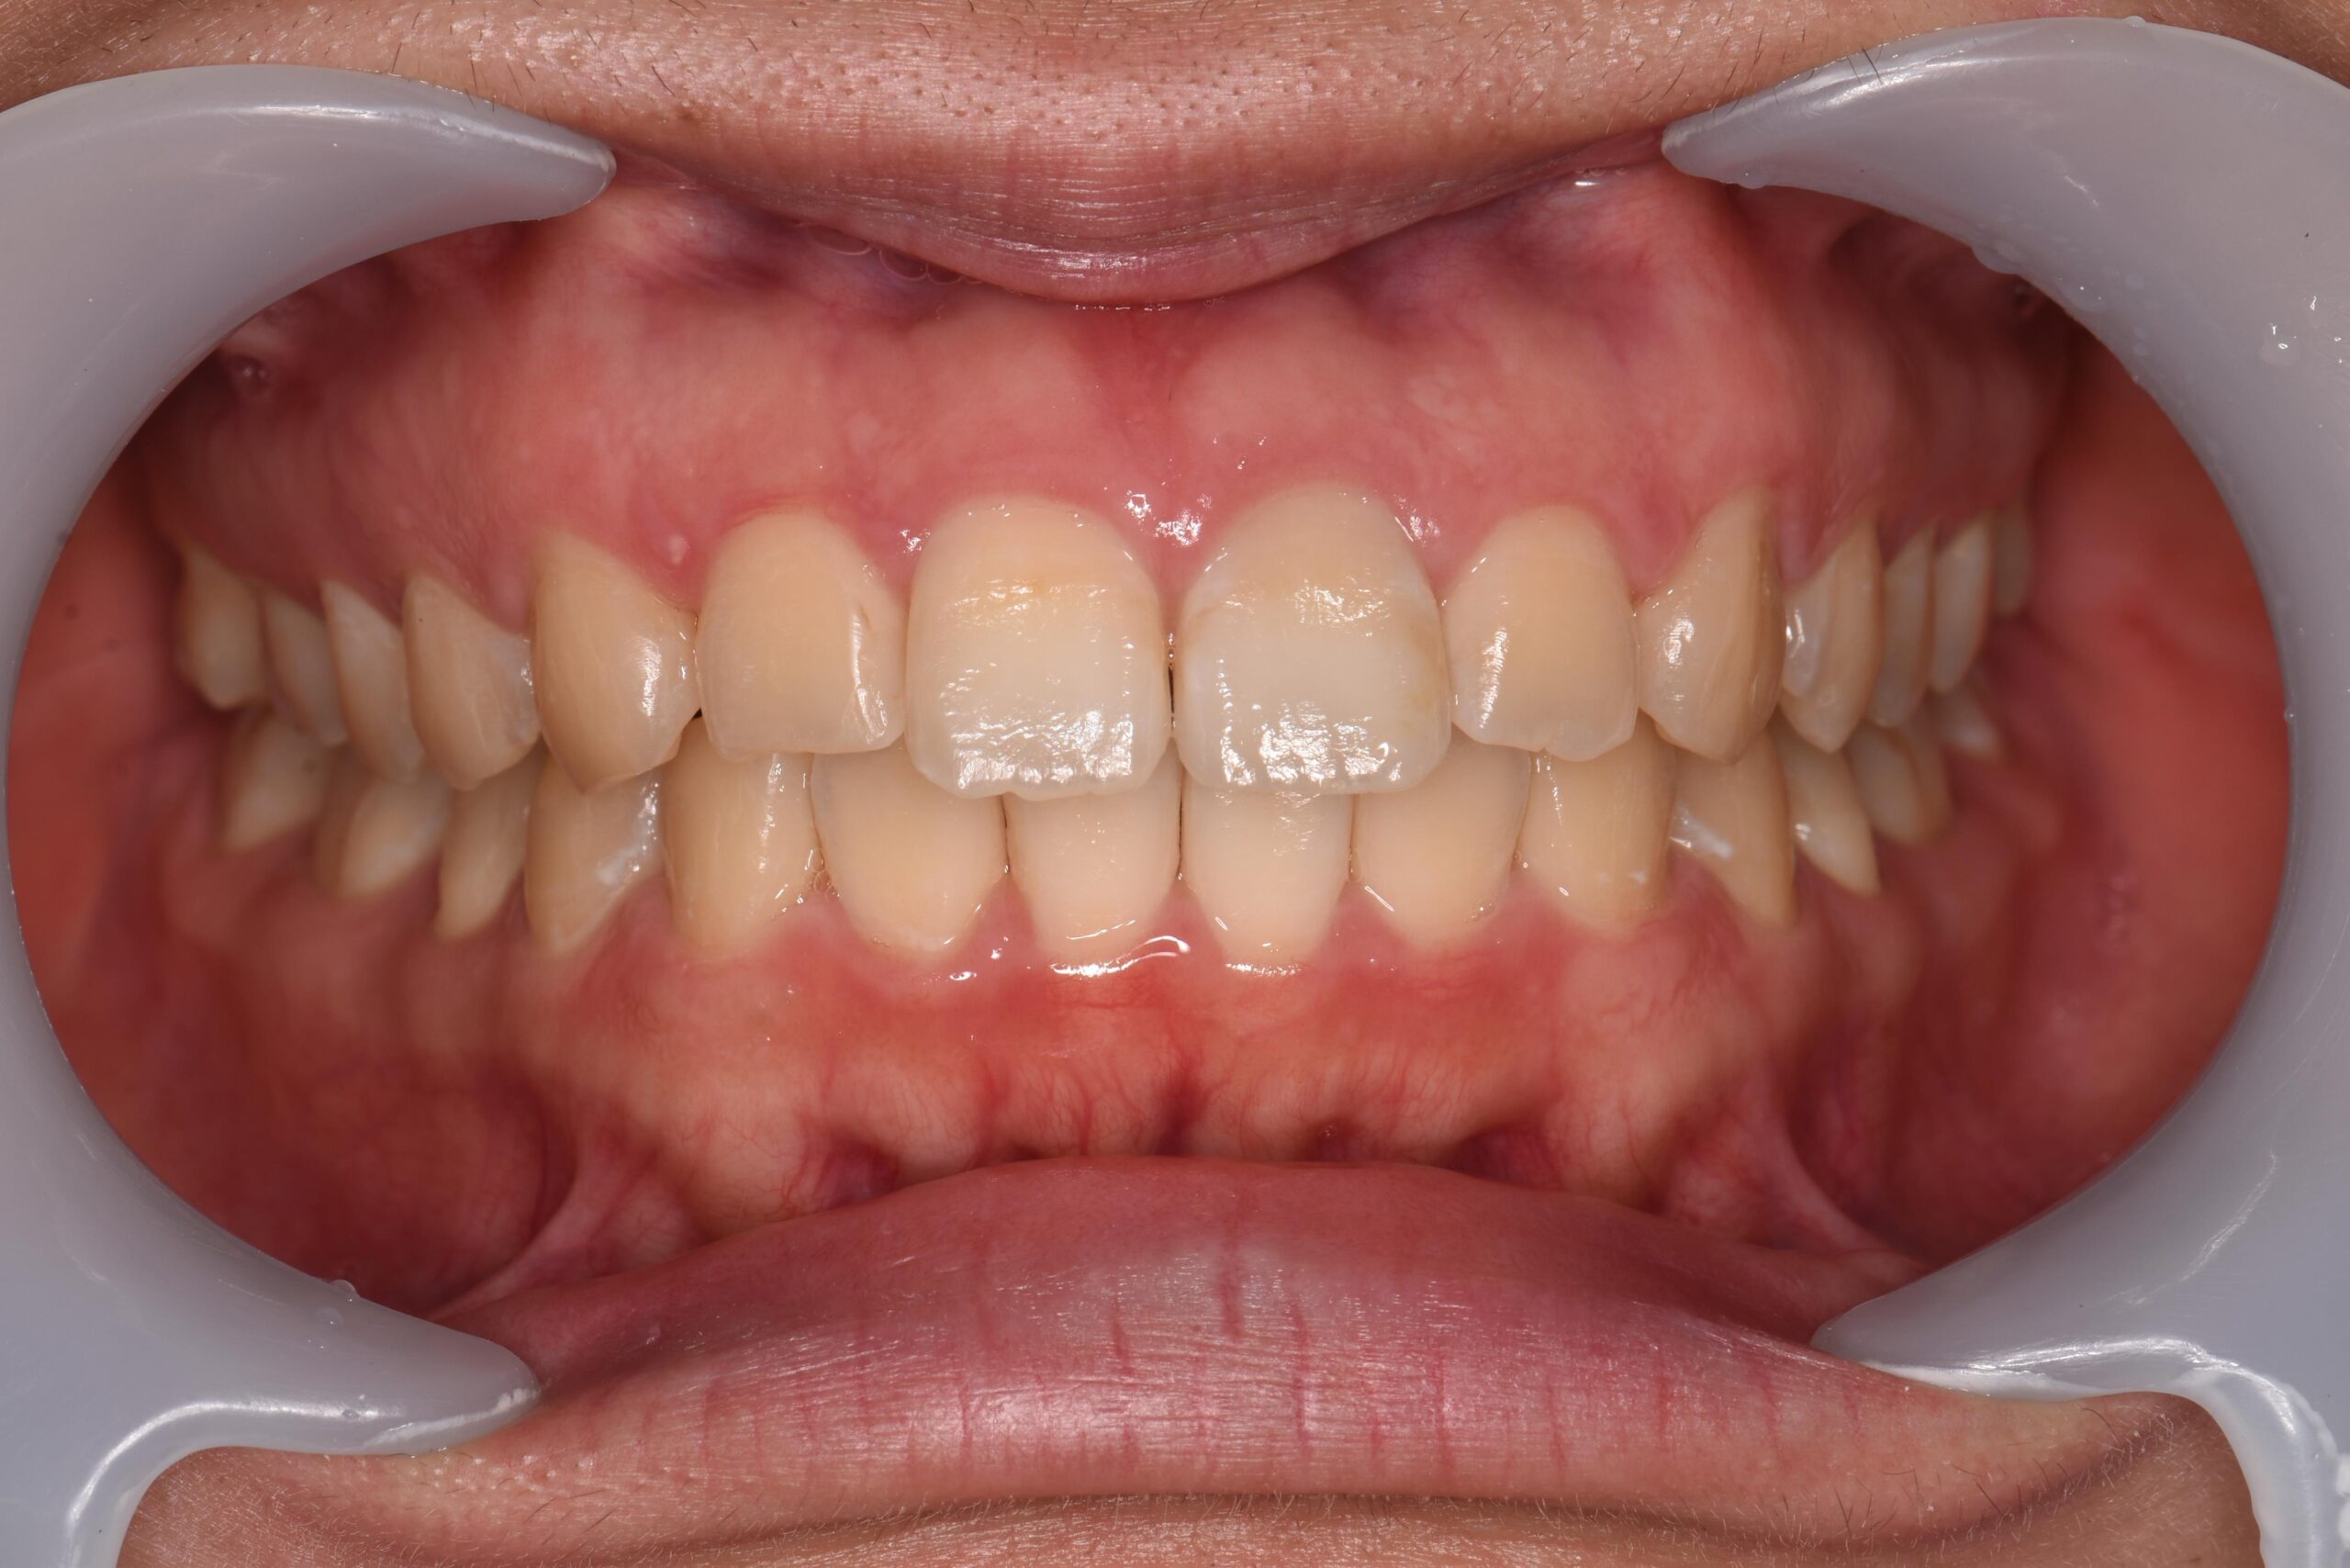

歯と歯の間に隙間がある状態です。

食事のときにうまく噛みきれなかったり、食べ物が歯に詰まりやすくなるなどのデメリットの他に、歯と歯の間から空気が抜けることで、発音にも支障が出るケースもあります。